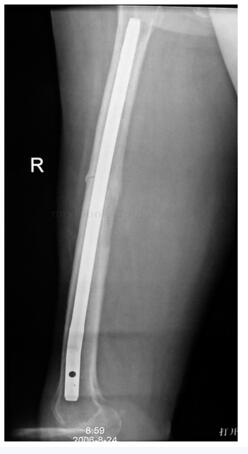

:患者术后3周开始扶双拐下地运动,并进行大腿局部放疗1月。术后半年,患者轻微外伤后出现右股骨干中段横断骨折,因有预防性内固定存在,骨折无移位(图49‐8),术后1年骨折愈合(图49‐9)。目前患者术后5年,肿瘤无局部复发,无淋巴结转移,无远隔转移(图49‐10)。患者平卧位主动屈髋、屈膝无力,被动屈膝45°,屈髋45°,日常不佩戴支具扶单拐行走,也可以不扶拐行走,轻度跛行。患者自觉功能满意。

图49‐10 术后5年复查